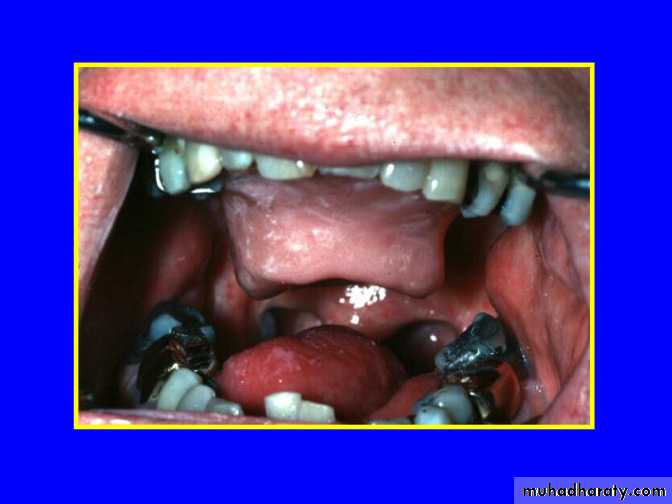

For Glossectomy DefectsGlossectomy Defect

Malignant tumors of the tongue, floor of the mouth &/or the mandible often require extensive resection of the tongue.Glossectomy, an extremely disabling surgical procedure. Affect the neuromuscular coordination of the tongue that plays an important role in 3 functions: mastication, swallowing and speech.

The nature of disabilities is dependant upon the volume & site of resected tissues, impact of radiation, motor & sensory control of the remaining tongue.

Tongue defects due to tumor removal can result in either…… total or partial glossectomy.

• Amount & position of the tongue remaining part(s).• The retaining means (teeth, denture or implants) are very important especially in patient with total glossectomy .

• The procedure combines with the glossectomy (eg. Mandibulectomy, palatectomy, radiation therapy).

• The condition of surrounding structures.